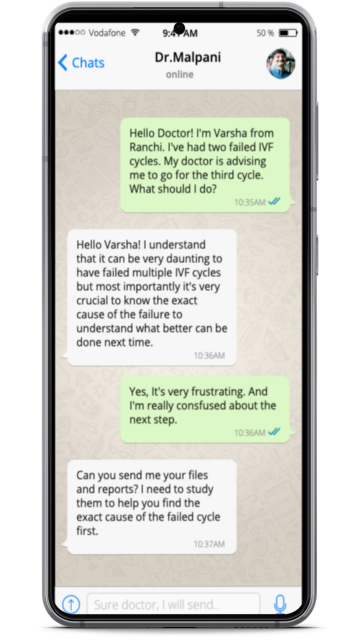

IVF made easy with our new chatbot - Powered by ChatGPT

Who doesn’t love a free consultation? Yes, you heard it right. All your queries on IVF will be answered by Chatbot and it’s completely free. No conditions attached.

IVF technology and procedures are constantly evolving, so we continuously update our chatbot with the latest information and advancements. It is powered by the latest AI technology. ChatGPT

Our chatbot is designed to provide clear and concise answers to questions using simple and easy-to-understand language.

This can help you become better organised, and a well-informed patient gets better medical care!

You can chat with our Chatbot in your own leisure time and don’t have to worry about spending too much time, resources or money on the consultation.

Infertile Patients are often confused. They get so much conflicting information from so many different sources.

The more you know easier it is for your IVF doctor to help you and the easier it will be for you to shield yourself from all the myths and misconceptions which hundreds of people will bombard you, so the only way to protect yourself is by investing in information therapy. The good news is all of these questions will be answered through Chatbot for free by IVF Expert Chatbot.

The team of Experts behind IVF India Website.We love to help patients to be more informed. We will help to ask the right questions and answer all of them through WhatsApp